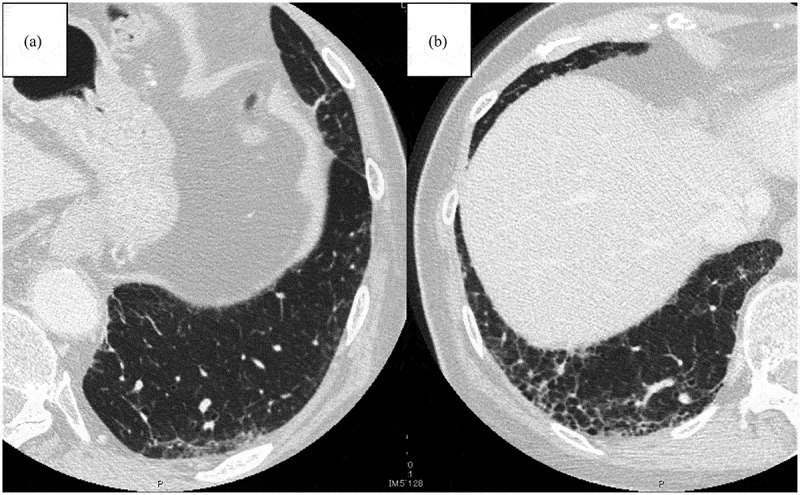

免疫疗法彻底改变了非小细胞肺癌(NSCLC)的治疗前景,显著提高了患者的生存结果,并为患者带来了新的希望。然而,NSCLC患者间质性肺异常(ILAs)的存在带来了独特的挑战,特别是由于免疫检查点抑制剂(ICI)相关肺炎的风险升高,这可能导致治疗中断并对预后产生不利影响。通常在计算机断层扫描成像中偶然发现的ILAs与间质性肺疾病进展的风险增加有关,并且已被确定为接受免疫治疗的非小细胞肺癌患者临床预后不良的潜在预测因子。这篇综述综述了目前对ILAs和ICI治疗之间相互作用的理解,讨论了患病率、放射学特征、风险分层和管理策略。此外,它强调需要前瞻性、多中心研究来建立具有ILAs的非小细胞肺癌患者的最佳治疗方式,以确保更安全、更有效的免疫治疗。

Immunotherapy has revolutionized the treatment landscape of non-small cell lung cancer (NSCLC), significantly improving survival outcomes and offering renewed hope to patients. However, the presence of interstitial lung abnormalities (ILAs) in patients with NSCLC presents unique challenges, especially due to the elevated risk of immune checkpoint inhibitor (ICI)-related pneumonitis, which can result in treatment interruptions and adversely affect prognosis. ILAs, often detected incidentally on computed tomography imaging, are associated with an increased risk of progression to interstitial lung disease and have been identified as a potential predictor of poor clinical outcomes in patients with NSCLC receiving immunotherapy. This review offers an overview of the current understanding of the interaction between ILAs and ICI therapy, discussing prevalence, radiological features, risk stratification, and management strategies. Additionally, it highlights the need for prospective, multicenter studies to establish optimal treatment modalities for patients with NSCLC having ILAs, to ensure safer and more effective immunotherapy.